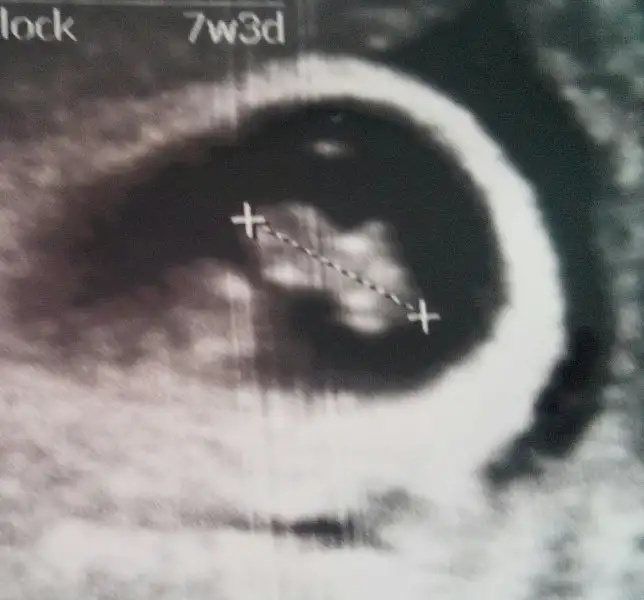

canım bunlar da 6 haftalık..şimdiden sabrın için teşekkür ederim...:)Cnm hep söylüyorum 9 haftalar kese için büyük 6,7 haftalık foto at

canım bunlar da 6 haftalık..şimdiden sabrın için teşekkür ederim...:)

Tamam canım hemen bulayım onlarıCnm hep söylüyorum 9 haftalar kese için büyük 6,7 haftalık foto at